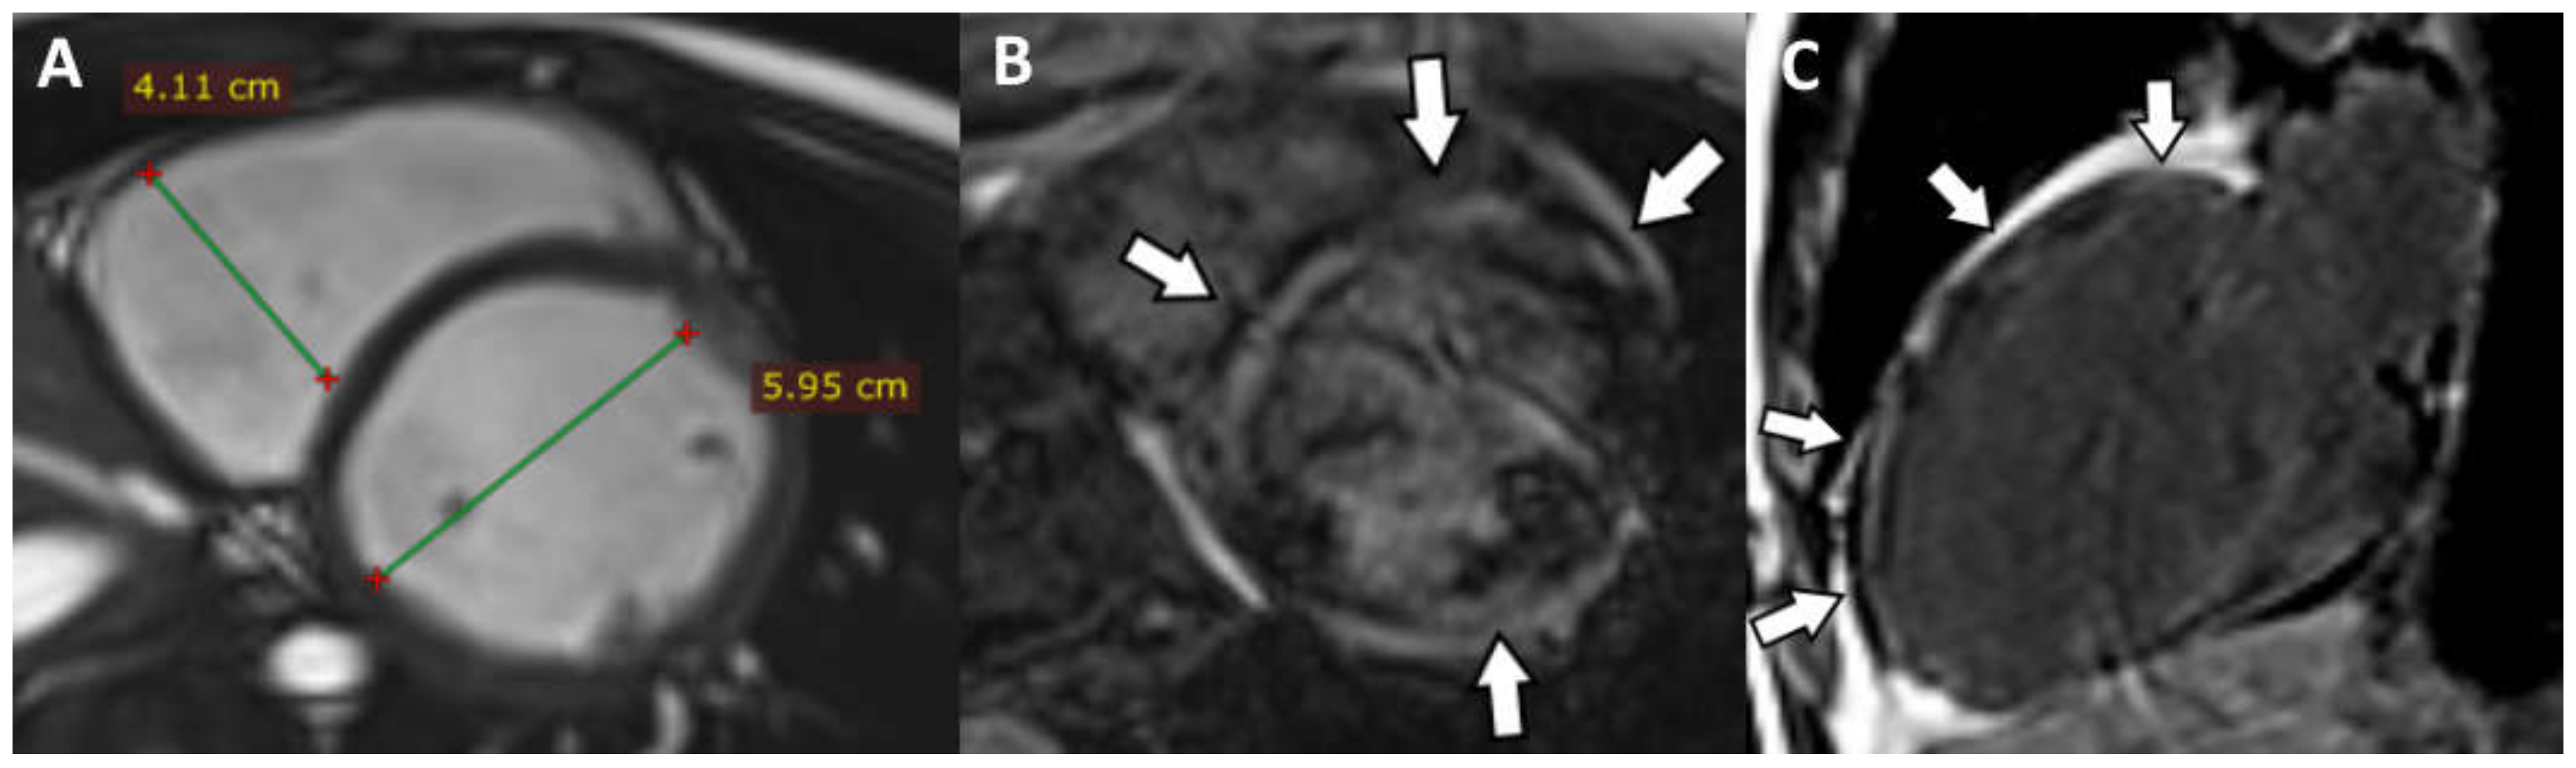

The CMRI highlighted the following: biventricular dilatation (LV = 52/58 mm; RV = 53 mm short axis base), global hypokinesia of the LV and RV, with small akinetic area in the IVS (Figure 4D), focal dyskinetic areas in the RVOT (Figure 4A), anterior wall of the LV (Figure 4B) and RV apex (Figure 4C). LGE confirmed the extended biventricular fibrosis of the myocardium, which showed a midmyocardial, concentric distribution in the LV, starting from the basal up to the apical segments (Figure 4E,F). Focal contrast enhancement alternating with areas of normal myocardium were noticed in the walls of the RV. The ventricular function is severely altered (LVEF = 22.6%; RVEF = 27.2%, EDV/S = 123 mL/m2)—major MRI criteria for the diagnosis of ARVC.

Figure 4. (A) Axial Cine-GRE sequence: focal dyskinesia of the RVOT; (B) Cine-GRE two-chamber LV sequence: focal dyskinesia of the anterior wall of the LV; (C,D) four-chamber Cine-GRE sequence: focal dyskinesia of the RV apex (arrow), dyskinesia of the lateral wall of the LV (square brackets), akinetic IVS areas (black arrows); (E) PSIR sequence—delayed postcontrast axial view: concentric midmyocardial LGE within the LV and diffuse, inhomogeneous LGE of the lateral wall of RV; (F) PSIR sequence—delayed postcontrast short axis view: midmyocardial LGE of the LV base.